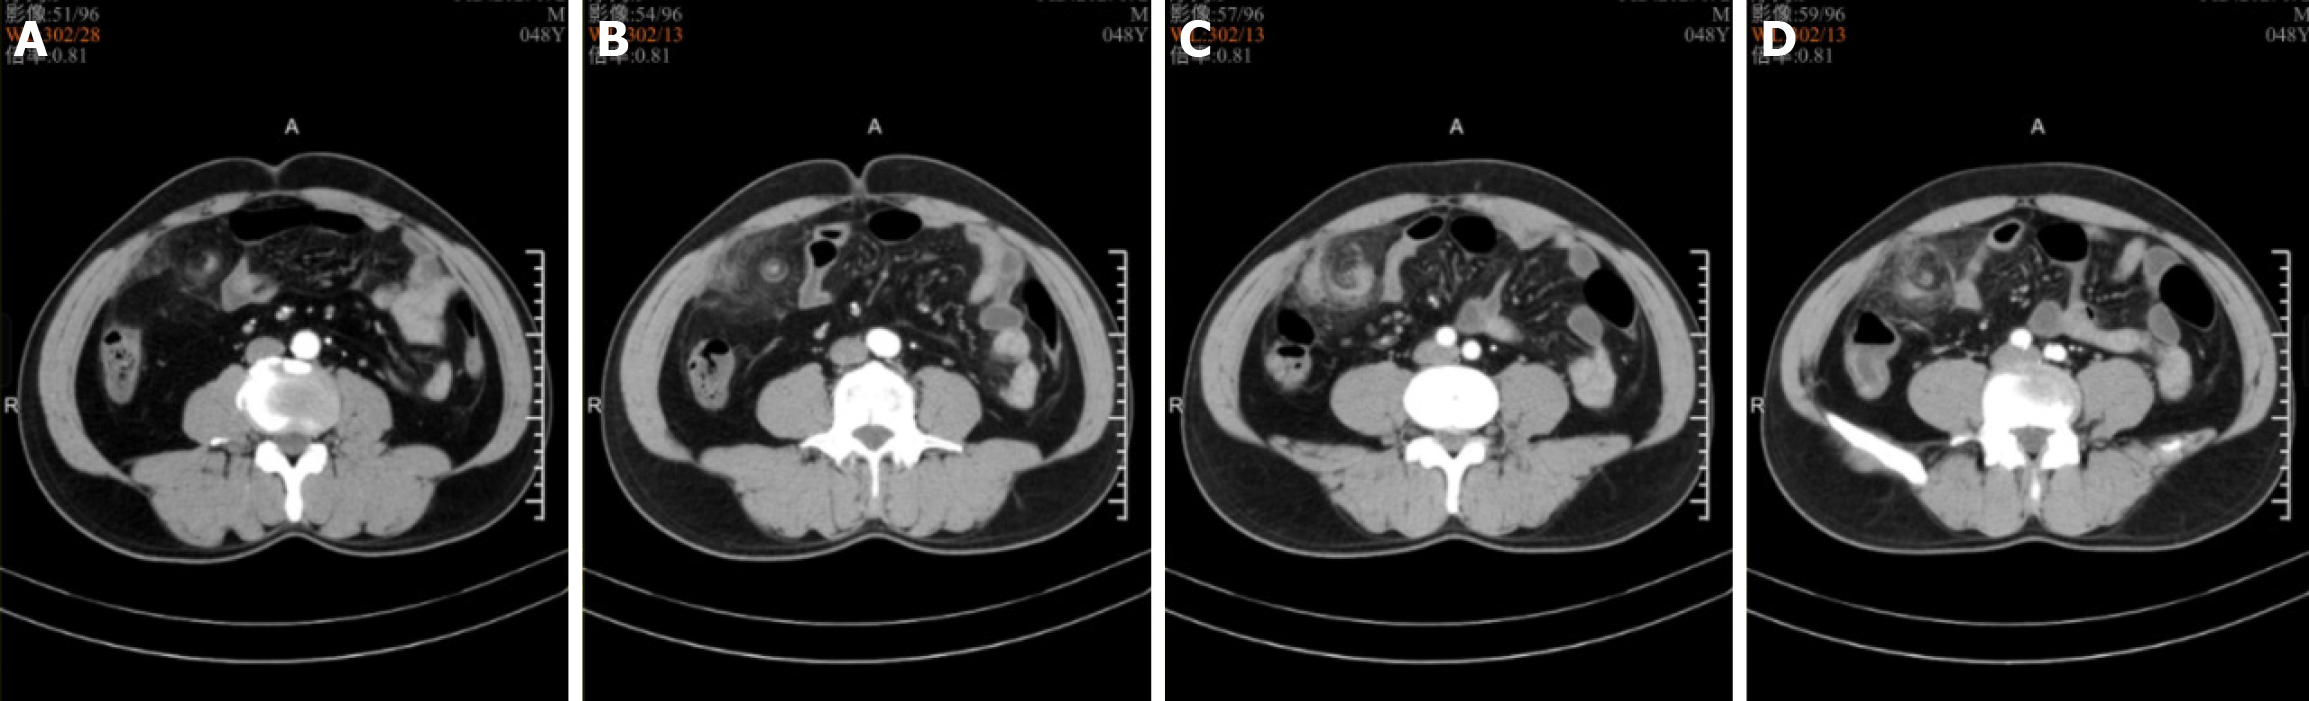

Contrast-enhanced CT revealed thickening of the omentum in the right abdomen, with the omentum twisting spirally along its axis and having blurred edges (Figure 1).

The greater omentum, a four-layered fold of peritoneum containing connective tissue, fat, lymphatics, and rich blood vessels, helps to limit the spread of diseases. Fewer than 300 cases have been reported in the literature[2]. OT is classified as either primary or secondary. POT is associated with factors such as obesity, anatomical variants (e.g., tongue-like or bifid omentum), and sudden increases in intra-abdominal pressure, while secondary OT is commonly linked to hernias, tumors, cysts, and surgical adhesions[3]. OT predominantly occurs on the right side, possibly due to the greater size and mobility of the right-sided omentum relative to the left-sided omentum[4]. The outcomes of OT depend on the degree, duration, and vascular compromise of the torsion. The torsion first obstructs the venous return, leading to distal omental edema. Although this may resolve spontaneously, it can progress to a bloody exudate. Persistent torsion causes arterial occlusion, which can lead to omental necrosis, followed by systemic toxemia resulting from toxic byproducts. Early OT presents with periumbilical or epigastric pain arising from autonomic nerve irritation, low-grade fever or normal body temperature, nausea and vomiting, and localized abdominal tenderness, although bowel sounds are typically normal. As OT progresses, peritonitis develops from the omental ischemia and necrosis, and pain becomes localized to the lesion site, with rebound tenderness and muscle strain detected during a physical examination. OT covering a large area may present as a palpable abdominal mass. X-ray and ultrasound examinations lack sensitivity and specificity for OT diagnosis. Typical ultrasound findings include a hyperechoic, noncompressible ovoid mass near the peritoneum with no blood flow signal[5]. CT is the primary imaging modality for OT. It typically shows the swirl sign (also known as the whirlpool sign), appearing as linear streaks of thickened omental vessels twisted spirally along a single axis[6,7]. Compared with plain CT, contrast-enhanced CT can better visualize the centra vascular structure of the mass, thus improving the diagnostic accuracy for OT[8].

As a rare condition with non-specific clinical features, diagnostic imaging is pivotal for the identification of OT. Prompt abdominal CT is crucial for OT diagnosis, and it typically shows the swirl sign. Compared with plain CT, contrast-enhanced CT can better visualize the central vascular structure of the mass. Laparoscopic surgery is a safe and effective diagnostic and therapeutic approach. Omentectomy usually results in favorable outcomes. The characteristics of OT are summarized in Table 2.